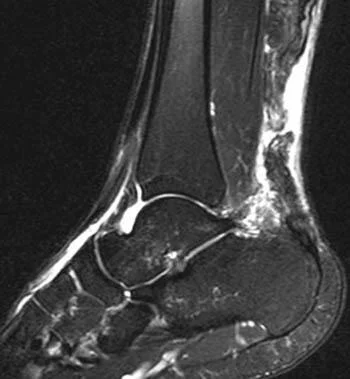

Diagnostic imaging – X-rays, CT scans, or MRI may be ordered to rule out other causes.